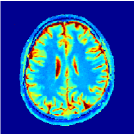

Two sets of experiments were conducted here: first, we used the 2D and 3D acquisition sequences for scanning a healthy volunteer’s brain (real-world acquisitions). Figures 6 and 7 display the parametric maps reconstructed from 2D spiral and radial readouts. We computed the T1, T2 and proton density (PD) maps using baseline reconstruction algorithms ZF, VS, LR, FLOR, AIR-MRF and our proposed LRTV. While baselines use DM either for quantitative inference or also during reconstruction (i.e. AIR-MRF), we further compare the DM-free LRTV’s performance when cascaded to DM, KM and MRFResnet for quantitative inference. For the 3D spiral acquisitions we compared LRTV and its closest competitor VS in Figure 8. Outcomes from other tested algorithm are displayed in the supplementary materials (Figure S5). Since FLOR does not use dimensionality-reduction, our system ran out of memory during 3D reconstruction; hence results are not reported in this case.

The LRTV-DM and LRTV-MRFResnet perform on par, and both outperform all tested baselines for reconstructing T1, T2 and PD maps in all acquisition schemes. This can be observed both visually in Figures 6, 7, 8, S2 and S3, and quantitatively in Table IV across all tested metrics. Other baselines were unable to successfully remove the under-sampling artefacts in TSMIs, and these errors propagated to the parameter inference phase and resulted in inaccurate maps. Temporal-only priors incorporated within LR are shown insufficient to regularise the inverse problem and LR sometimes (e.g. 2D spiral acquisitions) can admit solutions with even stronger artefacts than the model-free ZF baseline. This issue was previously studied for other non-Cartesian MRF readouts that similar to our spiral/radial trajectories, miss to sample the corners of the k-space in all timeframes (see section 2.2.2 and figure 2 in [19]). In the absence of reference for the k-space corners information, the LR iterations despite minimising the objective can converge to solutions with high-frequency artefacts, as visible in the computed maps. This highlights the need for adding an appropriate spatial-domain regularisation. FLOR reduces the LR’s artefacts but this improvement is limited because the suggested nuclear norm penalty does not incorporate an explicit spatial regularisation. Further for reducing artefacts, FLOR can introduce an undesirable bias in the computed T1/T2 maps e.g. see error maps in Figures S2 and S3. The non model-based VS baseline incorporates spatial regularisation and results in spatially smoother maps than ZF and LR, but it is unable to output artefact-free images. Further and consistent with our in-vitro experiment, we observe that VS overestimates the T2 values (e.g. in White and Grey matter regions) in tested 2D acquisitions i.e. the spatial regularisation trades off agains the quantification accuracy. The model-based AIR-MRF adds spatial regularisation through 2D/3D low-pass Gaussian filters however this trades off the sharpness of the computed maps and can increase the errors at the tissue boundaries (we searched Gaussian spreads that keep the blurs and high-frequency artefacts minimal). For our acquisition readouts, Gaussian filters performed better than disk filters of [19] for avoiding strong Gibbs artefacts. On the other hand, the spatiotemporally regularised LRTV greatly improves the TSMI reconstructions i.e. 4 dB enhancement compared to the closest competitor baseline (Table IV). This enables computing accurate and aliased-free multi-parametric inference using DM or the DM-free learning-based alternative MRFResnet as visible in Figures 6, 7, 8, S2 and S3. MRResnet and DM score competitive quantitative inference results i.e. T1 and T2 MAPE less than 5% and 9%, respectively (Table IV). KM also outputs comparably accurate T1 maps, however this shallow learning model despite having a model size larger than MRFResnet, is unable to learn accurate T2/PD quantification and it results in poor estimated maps, consistent with our observations in section VI-C.